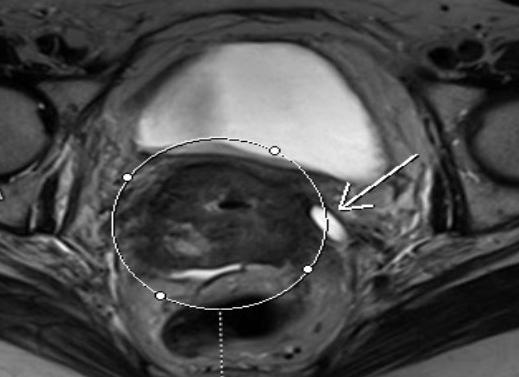

Метод магнитно-резонансного сканирования позволит не только определить наличие злокачественного новообразования, но также даст информацию о том, на какой стадии находится опухоль, какие изменения она вызвала в тканях, имеются ли прорастания опухоли в близлежащие ткани (прямую кишку или мочевой пузырь), имеются ли метастазы и где, в каком количестве.

Для успешного лечения рака шейки матки ответы на эти вопросы очень важны, так как они позволяют врачу принять решение о методе лечения, степени и глубины оперативного вмешательства при планировании удаления опухоли и т.п. На поздней стадии рака опухоль из шейки матки может прорастать не только в мягкие ткани органов малого таза (матку, мочевой пузырь, кишечник), но и может поразить брюшину, кости таза, позвоночник, лимфатические узлы.

Для оценки степени повреждений врач-диагност применяет метод введения контрастного вещества. Препараты вводятся внутривенно в кровеносную систему и разносятся с током крови, проникая в том числе и в опухоли и метастазы, на снимках они имеют яркое подсвечивание, позволяя оценить их наличие, количество, расположение, границы.

- Возможность выявления локализации опухоли, ее размеров и процесса метастазирования на МРТ при раке шейки матки, яичников и других детородных органах

Перед проведением магнитно-резонансной томографии матки пациент обязан сообщить рентгенологу о факте присутствия в организме инородных тел, так как многие имплантаты могут содержать в своем составе металл, а это является абсолютным противопоказанием к осуществлению обследования на томографе.На сегодняшний день многие медицинские устройства (например, внутриматочная спираль) изготавливаются их титана и других материалов, совместимых с МРТ. Поэтому, только врач будет принимать решение о возможности проведения данного вида обследования.Магнитно-резонансная томография с практически неограниченными возможностями в области функционального диагностирования способна выявлять разного рода заболевания, патологии, опухолевые образования.При подозрении врача на наличие у пациента онкологии, обязательно назначается МР томография. Так, диагностируя на МРТ рак шейки матки, врач проводит визуальный анализ распространенности злокачественной опухоли, изучает процесс метастазирования.В случае наличия метастаз на другие органы и ткани проводиться МРТ шейки матки с контрастом (специальным парамагнитным веществом), усиливающим диагностическую результативность данного обследования. Это необходимо сделать для того, что бы исключить возможность постановки ошибочного диагноза.Много заболеваний женских половых органов требуют точного диагностического обследования с использованием контрастного усиления. Но вот, проводить МРТ при миоме матки с контрастным веществом нет нужды, так как данное образование выявляется при первичном осмотре врача (матка увеличена в размерах).Диагностика придатков матки позволяет выявить рак яичников на МРТ, который может развиваться как на одном, так сразу и на двух яичниках. Женщинам старше 45 лет нужно обязательно раз в год проходить комплексное обследование.

МРТ при диагностике рака матки является более информативным способом, по сравнению с КТ. Глубина проникновения опухоли и переход ее на шейку матки более четко визуализируются на магнитно-резонансной томографии. В отношении определения наличия метастаз в брюшной полости и забрюшинного пространства, лимфатических узлах МРТ и КТ, как методы диагностики, имеют одинаковую информативность.